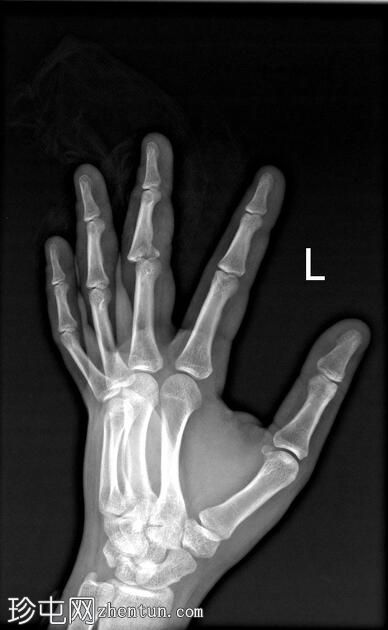

左

手外

伤。

X线片

斜位

可见第三指中节指骨基底部轻微移位骨折,延伸至近端指间关节(PIP关节),并伴有软组织肿胀。

第三指中节指骨基底部轻微移位骨折,延伸至近端指间关节(PIP关节)指骨,并伴有软组织肿胀。